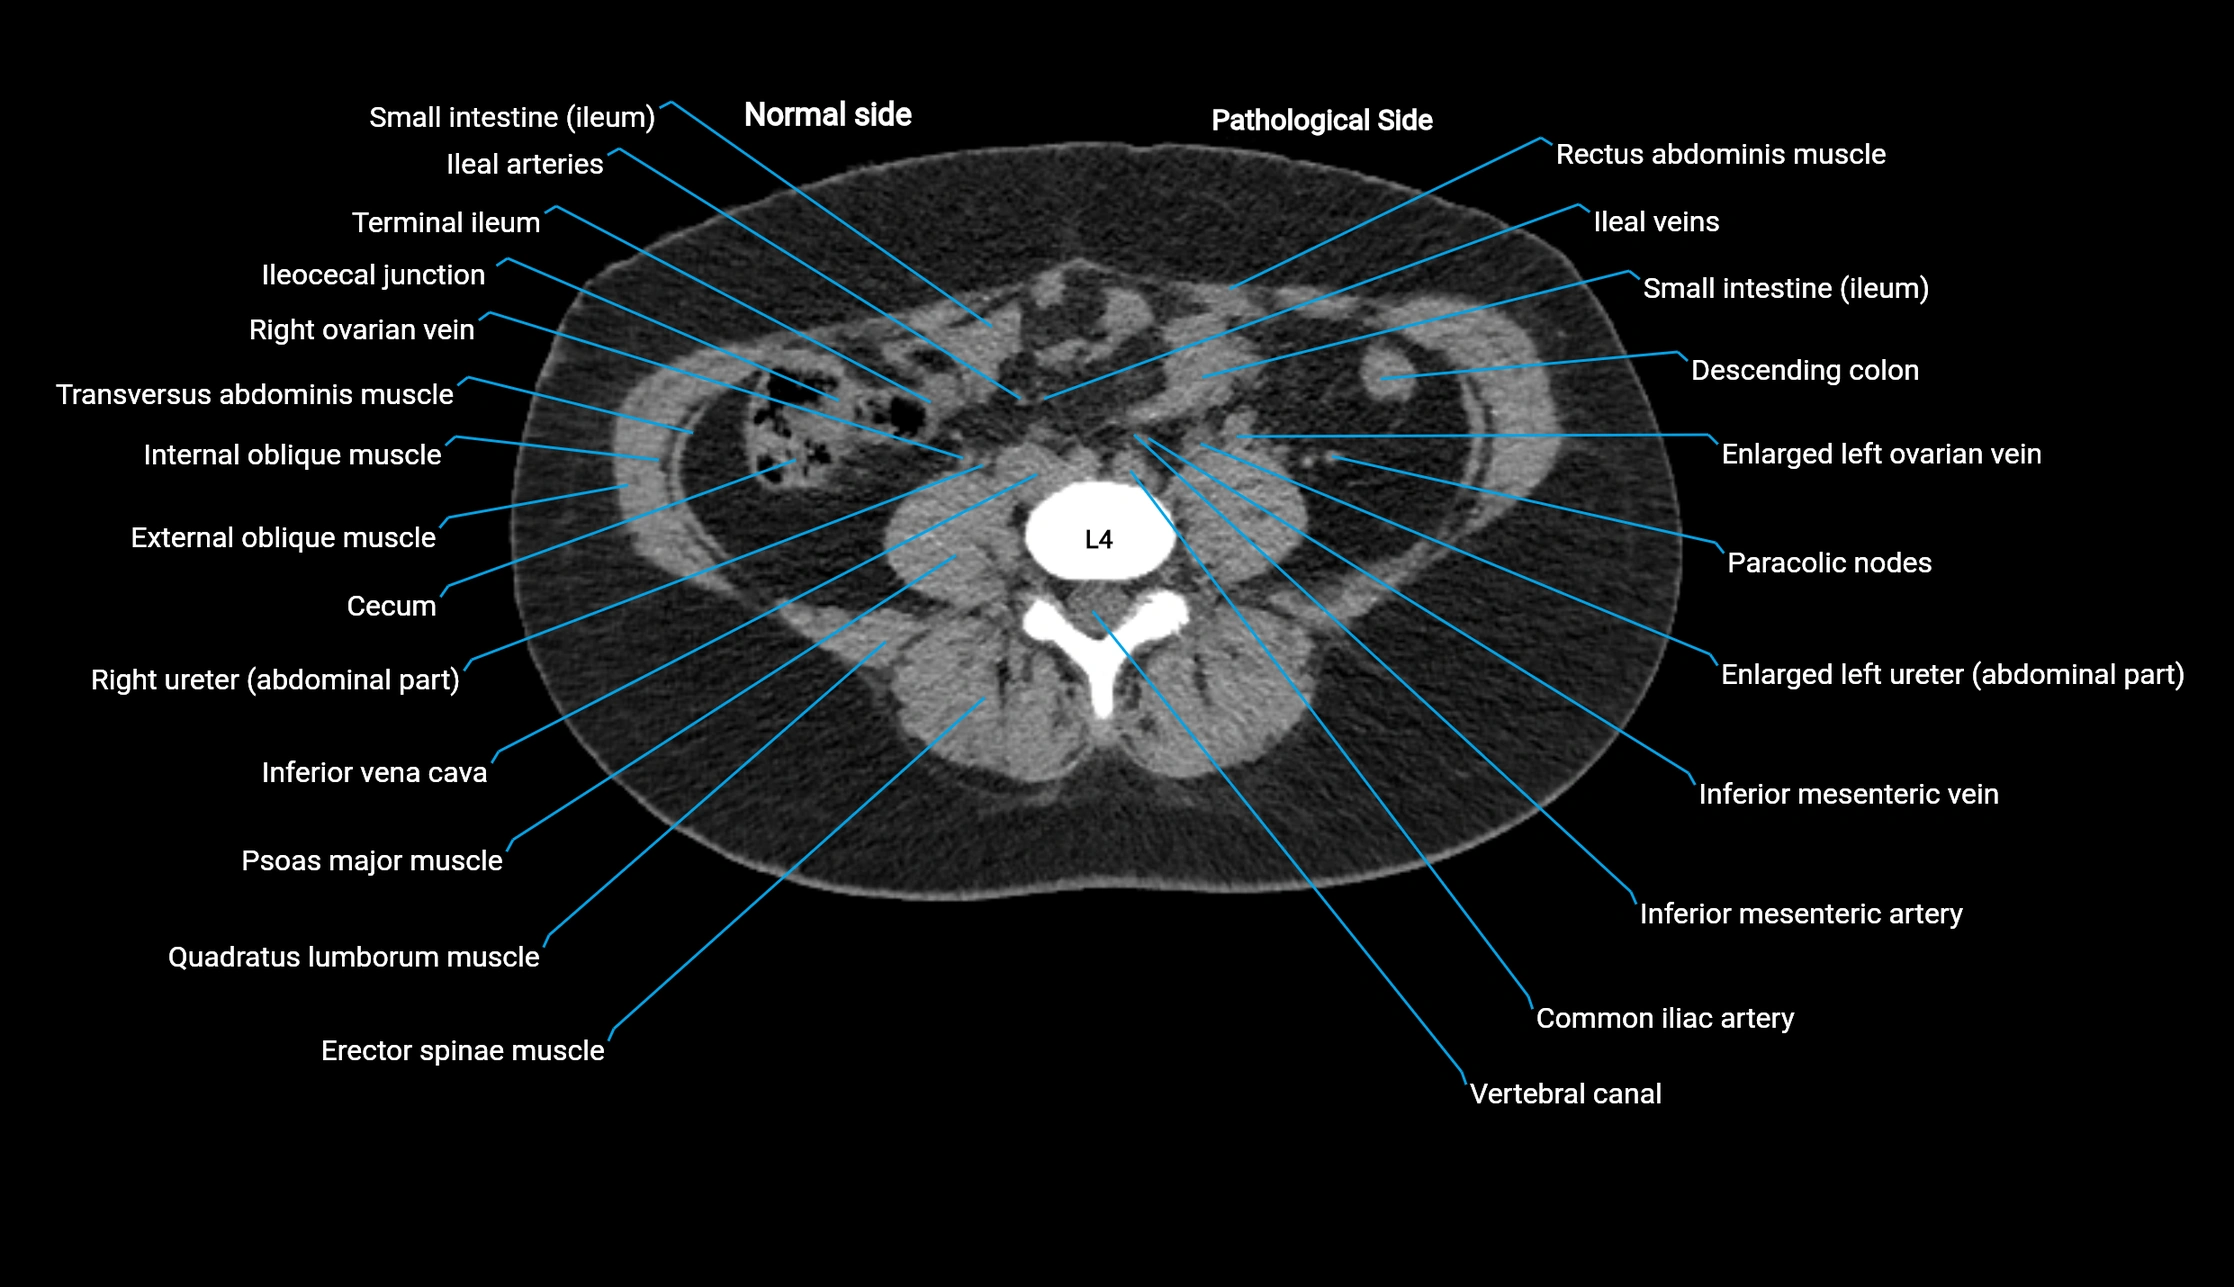

CT image

image